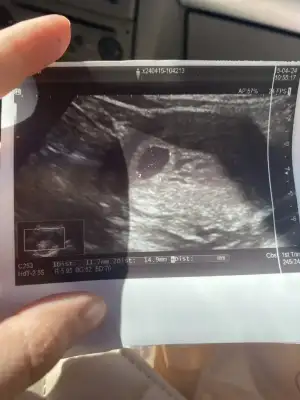

Sellaaam kızlar😍 6+3’ten selam doğumum 19 kasım 12 aralık görünüyor buraya katılmak istedimm bu da kesem kalp atışı için haftaya gidicem😍

Ya benim kesem biraz uamuk gibi geldi endişe ettim. Bende 30 nisanda kalp atışına gideceğim. Gittiğimde 7+2 olacağız